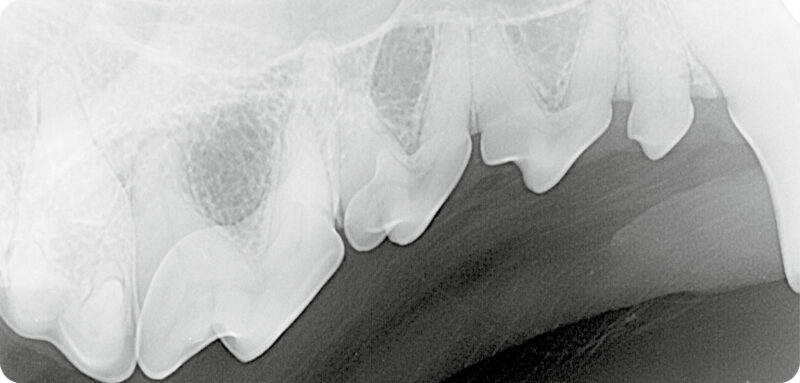

Röntgenbeispiel Hund: Dieser Röntgenbefund (Abb. 2) ergibt eine überzählige Wurzel (➡️) zwischen mesialer (m) und distaler (d) Wurzel des dritten Prämolaren (⭐️) im linken Oberkiefer. Dahingegen ist das Röntgenbild des Oberkiefers rechts unauffällig.